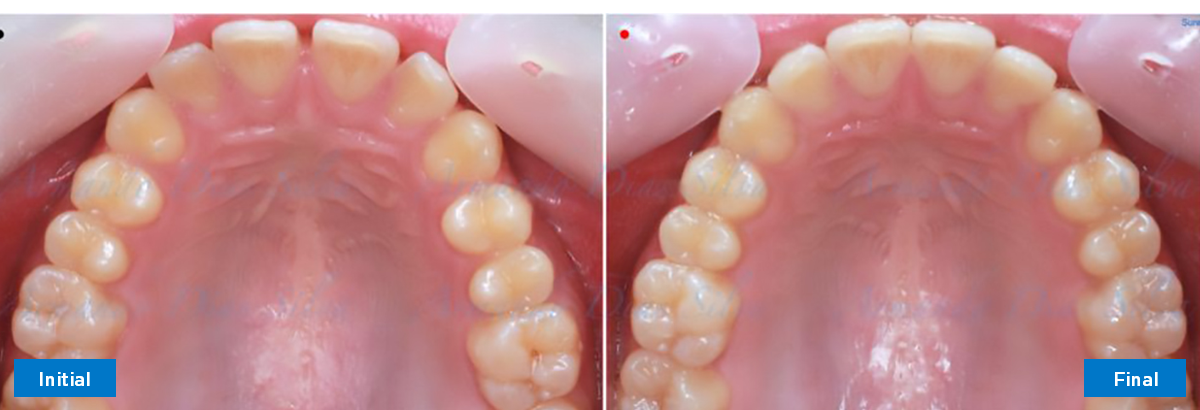

• Espaciamiento leve de las arcadas superior e inferior (deficiencia transversal de 3,45 mm)

• Deficiencia transversal maxilar leve (3,45 mm)

• Desrotar y distalizar los molares superiores

• Retruir los incisivos superiores

• Molares de clase I logrados con distalización y sin elásticos

• Sin expansión maxilar, respetando la envoltura periodontal